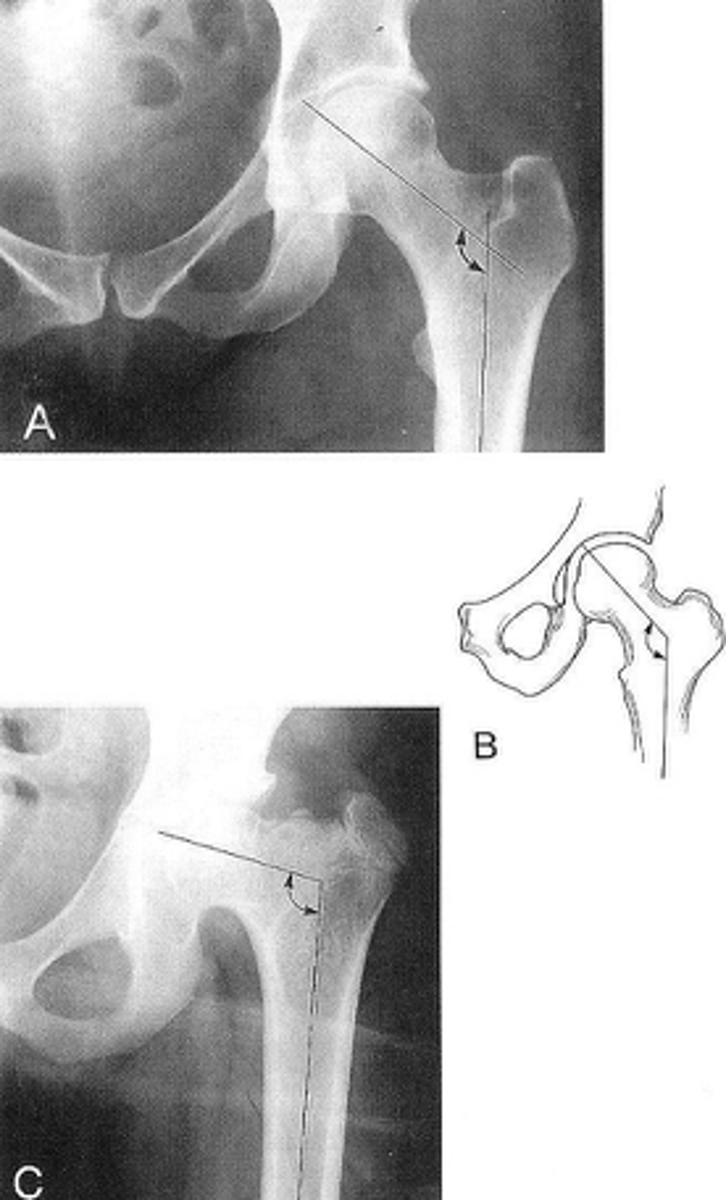

10

New cards

- AP hip

- Frog-leg (lateral) hip

State the standard unilateral hip projections

11